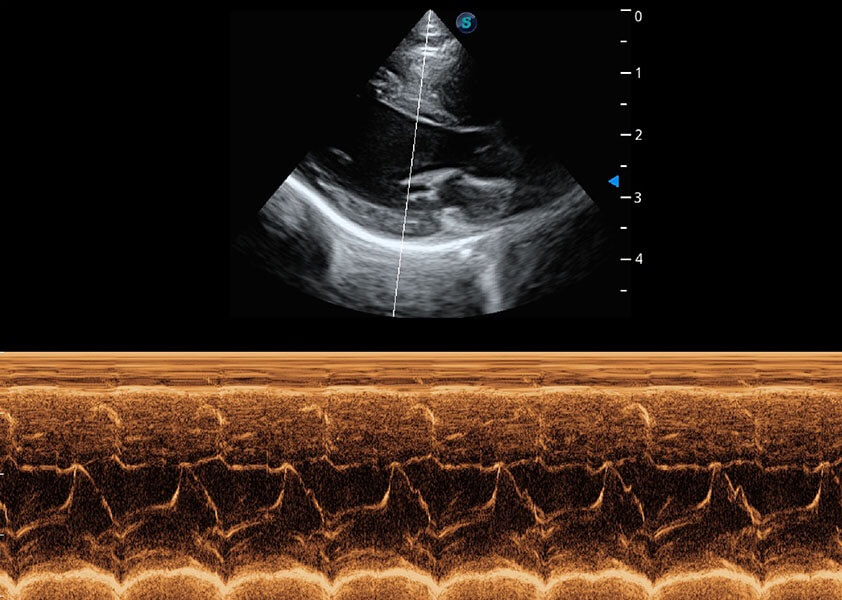

ProPet 60 作為一款高端臺式動物超聲設備,為動物醫(yī)生的日常診斷提供了一系列貼合動物臨床需求、解決臨床實際問題的高級成像功能。憑借全系列高清探頭,滿足醫(yī)生對腹部、心臟、生殖、淺表、肌骨等成像的所有需求,切實幫助您提升檢查效率,提高診斷信心。

動物是人類最親密的朋友和最值得信賴的伙伴。開立醫(yī)療也一直致力于探索動物專用的超聲影像解決方案。 全新推出的ProPet系列,是開立在動物超聲影像智能化、專業(yè)化、精準化的一次跨越式革新。動物不能用言語來表述自己的不適,通過超聲影像,ProPet系列搭建了動物醫(yī)生與不同物種溝通的“橋梁”,為動物醫(yī)生注入了“治愈之力”。